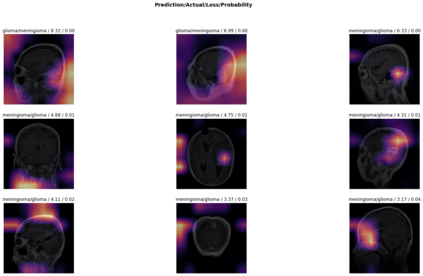

Magnetic Resonance Imaging (MRI) is a principal diagnostic approach used in the field of radiology to create images of the anatomical and physiological structure of patients. MRI is the prevalent medical imaging practice to find abnormalities in soft tissues. Traditionally they are analyzed by a radiologist to detect abnormalities in soft tissues, especially the brain. The process of interpreting a massive volume of patient's MRI is laborious. Hence, the use of Machine Learning methodologies can aid in detecting abnormalities in soft tissues with considerable accuracy. In this research, we have curated a novel dataset and developed a framework that uses Deep Transfer Learning to perform a multi-classification of tumors in the brain MRI images. In this paper, we adopted the Deep Residual Convolutional Neural Network (ResNet50) architecture for the experiments along with discriminative learning techniques to train the model. Using the novel dataset and two publicly available MRI brain datasets, this proposed approach attained a classification accuracy of 86.40% on the curated dataset, 93.80% on the Harvard Whole Brain Atlas dataset, and 97.05% accuracy on the School of Biomedical Engineering dataset. Results of our experiments significantly demonstrate our proposed framework for transfer learning is a potential and effective method for brain tumor multi-classification tasks.